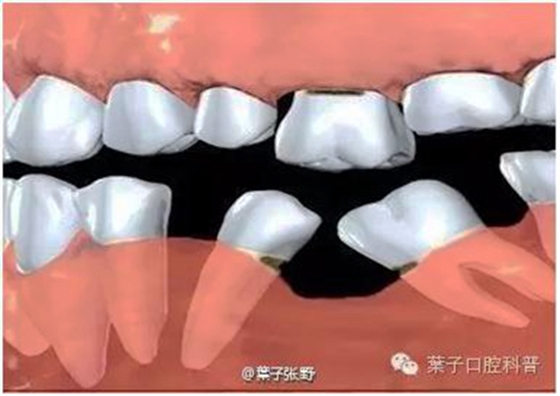

如果乳牙過早缺失,缺失牙齒臨近的其他牙齒可能向這個空隙移動或傾斜。而新長出來了恒牙,沒有了乳牙的引導,也會發(fā)生移動或錯誤地萌出。

乳牙缺失致恒牙“亂長”,這個“間隙保持器”可預防